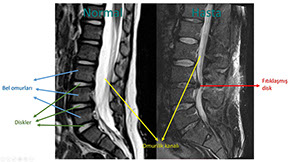

Yukardaki şekilde normal (solda) ile bel fıtığı olan bir hastanın (sağda) omurgalarının manyetik rezonans incelemeleri karşılaştırılmıştır. Filmleri incelerken yandan baktığımızı aklınızda tutun. Buna göre sağ taraftaki hastanın 3. ve 4. bel omurları arasındaki diskin bir parçasının yerinden çıkarak omurilik kanalına doğru yer değiştirdiğini ve bu bölgedeki sinirlere baskı yaptığını görebilirsiniz.

Tanıda manyetik rezonans incelemesi önemli bir yer tutar.

İnsan omurgasında çok sayıda bağımsız "omurlar" bulunur. Bu omur kemiklerinin arasında birbirlerine sürtmelerini engelleyecek ve omurgaya hareket kabiliyeti kazandıracak küçük yastıkçıklar vardır. Bu yastıkçıklar "intervertebral disk" veya kısaca "disk" olarak adlandırılırlar.

Bu disklerin yaş ilerledikçe iç yapıları bozulur ve bu durum "dejenerasyon" olarak adlandırılır. İç yapısı bozulan bu diskler üzerlerine binen yükün de etkisi ile elastikiyetlerini kaybederler ve bulundukları eklemden dışarı taşarlar.